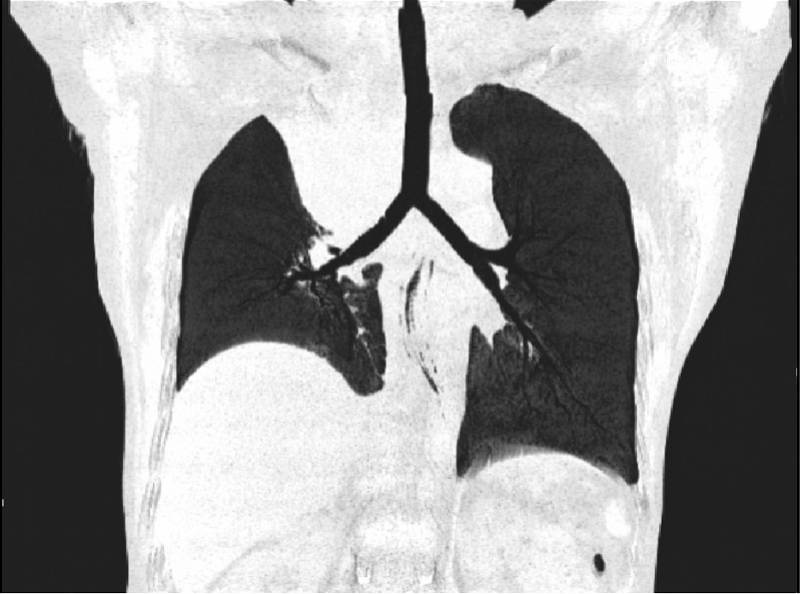

手术当天 , 林小玲副主任医师硬质支气管镜结合可弯曲支气管镜观察到阿云的肿瘤组织已经严重侵犯气管下段 , 隆突和右主支气管消失 , 左主支气管开口的黏膜也已经受到影响 , 情况比CT所见更加严重和棘手 。 林小玲副主任医师使用硬镜铲切部分气管内肿瘤后 , 再通过各种工具和器械小心翼翼地清除右主支气管腔内的肿瘤组织 , 最终重新暴露隆突和右主支气管开口 , 并打通右中间干支气管到达右中下叶支气管开口 , 在气管内置入一个Y型硅酮支架 , 在右主支气管—右中间干支气管置入一个金属半覆膜支架 , 成功重建气道 , 一方面保证了左肺通气 , 另一方面也恢复了右中叶和右下叶支气管的通气 。

术后 , 阿云恢复了右肺右中叶和右下叶支气管的通气